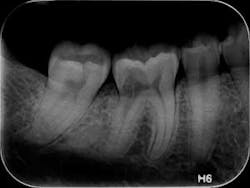

- Figures 9 and 10 show a discontinuation of the uniform outline of the pulpal chamber of tooth No. 19. Furthermore, margins of the lesion are sharp and well defined.

- Diagnosis: internal resorption.